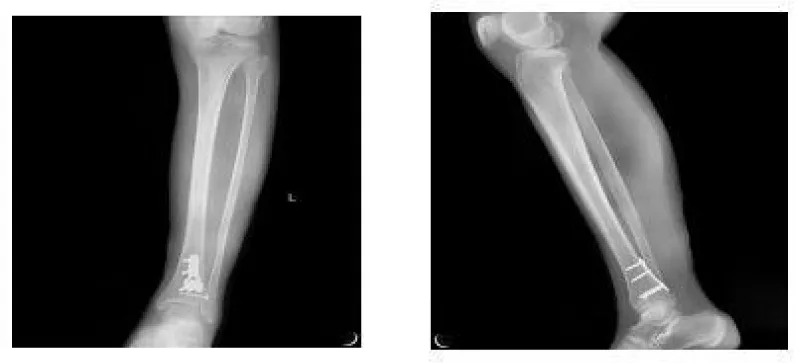

A 56-year-old woman was sent to the emergency department by her family. She sprained her left ankle when she went down the stairs. She had difficulty walking because of a painful left ankle. Specialized physical examination found tenderness in the anterolateral distal tibia and fibular neck. X-ray showed fractures in the tibia lateral border and fibular neck, with no evidence of inferior tibiofibular joint dislocation (Figures 1,2). A computed tomography scan confirmed the presence of Tillaux-Chaput and Volkmann fractures (Figures 3-5).

The anesthetic for the operation was lumbar anesthesia. A posterolateral approach was used to expose the Volkmann fracture. An anterior tibial approach was used to expose the Tillaux-Chaput fracture. The inferior tibiofibular joint was checked carefully. Fractures were reduced and then fixed. Volkmann fracture was fixed by buttress plate, and Tillaux-Chaput fracture was performed by hollow screw. Hook test intraoperative was negative. Anatomical reduction and perfect stability were confirmed by X and CT postoperatively (Figures 6.7). CT scan in the transverse section confirmed that the anterior and posterior edge of the distal fibula is in an arc with the fractures of the tibia. It meant there was no dislocation of the distal fibula. The anterior and posterior ligaments of the inferior tibiofibular ligament are in good condition.